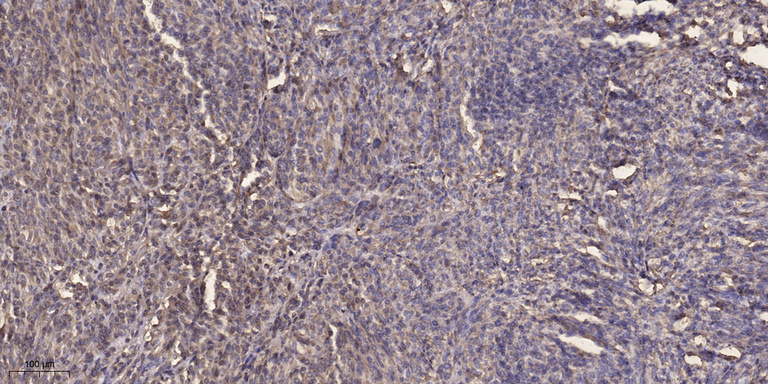

WB, IHC, IF, IP

Optimal working dilutions should be determined experimentally by the investigator; Suggested starting dilutions are as follows:IHC 1:50-300; IF 1:200.